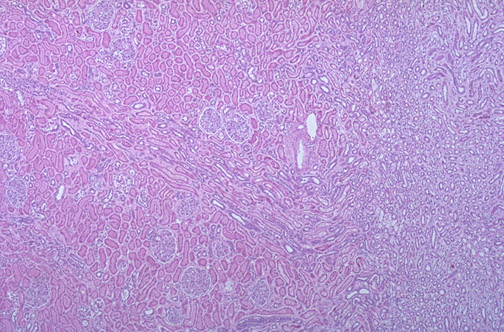

The corticomedullary junction of the kidney is seen here, with the

cortex

in which can be seen a

medullary ray (renal column)

extending to the medulla, and the

medulla

.